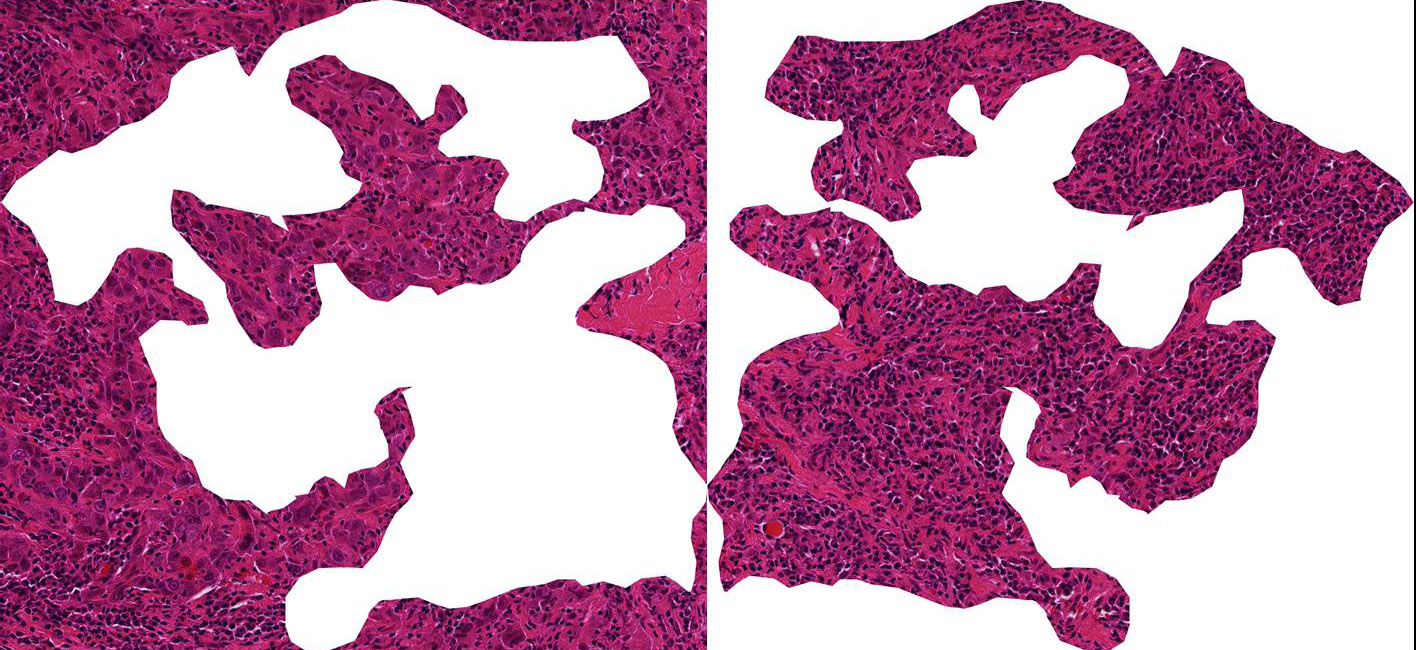

Schnitt durch Brustkrebsgewebe (Erklärung s. Text). © S. Wienert, C. Denkert, Charité

Bildunterschrift:

Schnitt durch Brustkrebsgewebe: Wenn Immunzellen (kleine dunkle Zellen) in den Tumor einwandern, haben Brustkrebspatientinnen gute Chancen, dass die Chemotherapie anschlägt. Das linke Bild zeigt hauptsächlich Tumorzellen (runde violette Zellen). Auf der rechten Seite sieht man, wie körpereigene Abwehrzellen (tumor-infiltrierende Lymphozyten, TILs) den Tumor infiltrieren (© S. Wienert, C. Denkert, Charité)